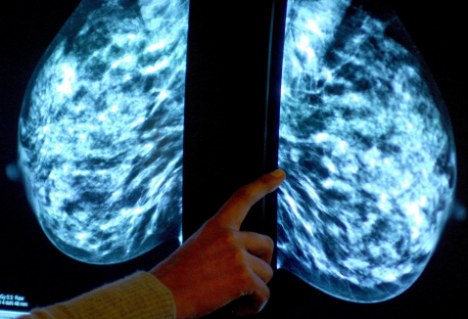

“原為尋找宇宙內超新星而設計的技術,現在正被用于癌癥的診斷。”據英國《每日郵報》網站3月10日報道,天文學家現與劍橋大學的腫瘤學家組成工作小組,將曾用來區分單個恒星和遙遠星系的電腦軟件用于檢測乳腺腫瘤的類別。

發表在《英國癌癥雜志》的一篇研究報告顯示,研究人員曾使用天文軟件來分析2000名乳腺癌患者的腫瘤情況。報告顯示,該軟件可作出與人類病理學家一樣準確的判斷,并在某些情況下,它得出的分析更加客觀。